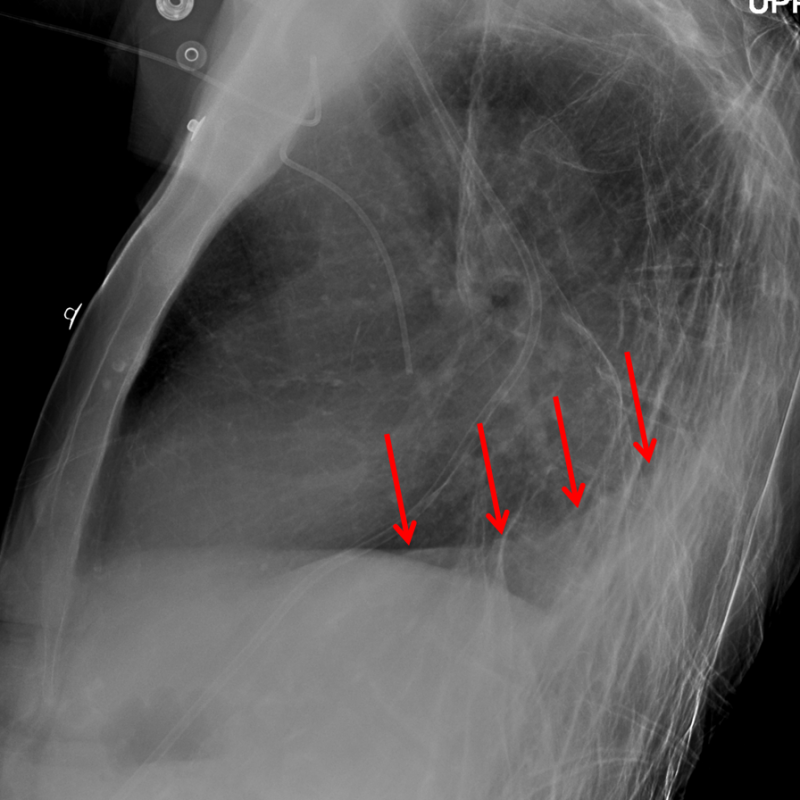

Age: 79

Sex: Female

Indication: Shortness of breath

Sample ReportRight lower lobe collapse with question of right hilar fullness. Recommend chest CT to exclude an obstructing hilar mass. Superimposed aspiration/pneumonia at the right lung base is not excluded, though the right basilar opacification could be entirely explained by lobar collapse.